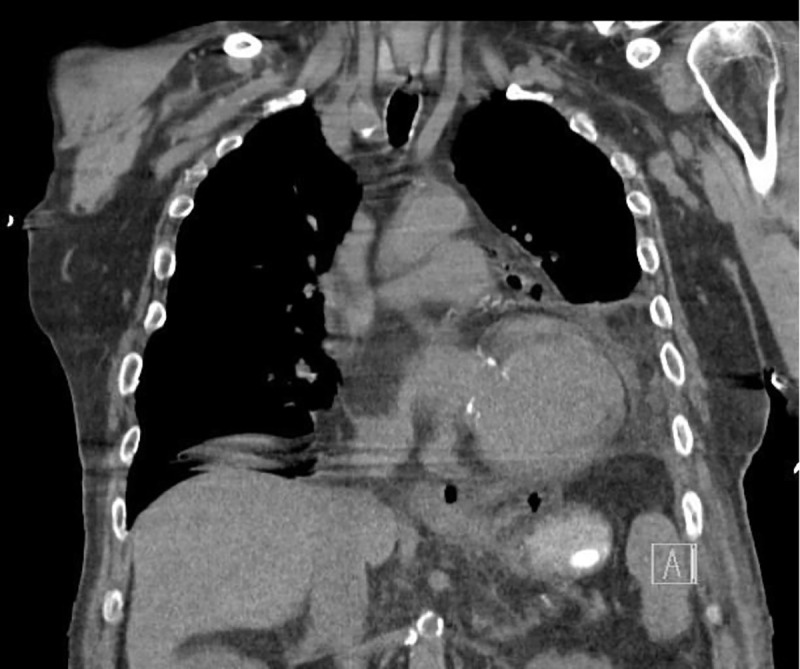

On admission day two, he developed acute abdominal distension and coffee ground emesis. Gastroenterology was consulted and further investigations into the patient’s history revealed vomiting with each episode of syncope. WBC at that time was elevated to 14.57 × 103 μ/L from his baseline of 7.21 × 103 μ/L on admission. Computed tomography with oral contrast revealed pneumomediastinum with a 3.6 × 6.9 cm air-fluid collection immediately adjacent to gastroesophageal junction on the left and several other foci of predominantly gas posterior to the gastric cardia which partially filled with small amount of contrast on postcontrast images (Figures 2–5). The diagnosis of esophageal perforation was made at that time. The patient was intubated, a nasogastric tube was inserted, and a temporary transvenous pacemaker was placed prior to transfer to our hospital for emergent repair of the esophagus.

Figure 2.

Coronal chest CT showing pneumomediastinum with left pleural effusion.